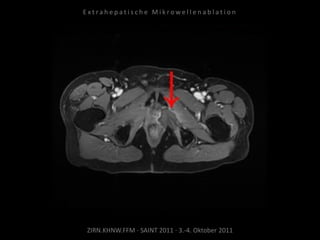

Metastase medial des linken

Musculus iliacus:

1 Nadelposition.

Erneute Ablation von 2 peritonealen

Metastasen am 09.09.2010.

Metastase kaudal der linken Niere:

Apikal 2 Nadelpositionen.

Kaudal 1 Nadelposition.

Metastase lateral der linken Niere: